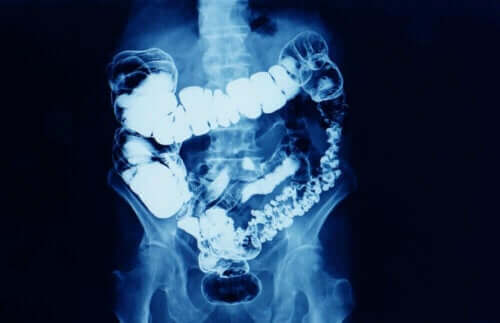

Vad är förstoppning?

I allmänhet betyder förstoppning att avföringsfrekvensen är reducerad. Förstoppning är ett symtom som innebär att tarmtransiten av någon anledning har minskat. Förstoppning drabbar fler kvinnor än män, särskilt kvinnor mellan 20 och 35 år och efter 60 års ålder.

Beroende på hur länge det varar kan förstoppning delas in i två typer:

- Tillfällig förstoppning: detta kan bero på förändringar i kost och vattenintag, brist på motion, behandling med vissa mediciner eller stressiga situationer.

- Kronisk förstoppning: För att läkare ska diagnostisera förstoppning som kronisk måste den vara i minst tre månader.

Man kan också relatera kronisk förstoppning till situationer som liknar de vid tillfällig förstoppning, men som varar längre. Andra gånger beror det dock på matsmältningsproblem och vissa sjukdomar.